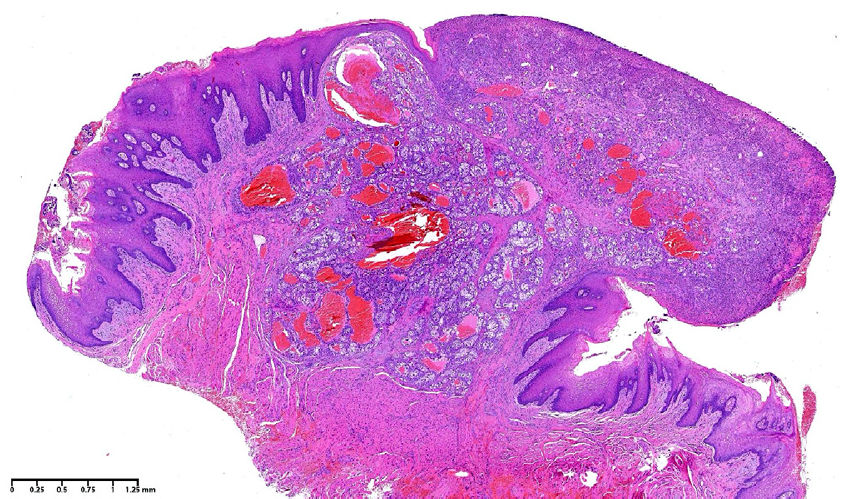

Фото 2. Микрофотография при малом увеличении, демонстрирующая отграниченную, неинкапсулированную пролиферацию атипичных полигональных эпителиальных клеток, погружённых в высоковаскуляризированную фиброзную строму (гематоксилин-эозин, увеличение ×2)

Гистопатологическое исследование выявило неинкапсулированную пролиферацию атипичных эпителиальных клеток, демонстрирующих компактный гнездный характер роста с очаговыми трубчатыми или микрокистозными структурами, погружёнными в богатую сосудистую фиброзную строму с участками кровоизлияний. Клетки поражения характеризовались прозрачной, вакуолизированной или бледно-эозинофильной цитоплазмой, чёткими цитоплазматическими границами, а также увеличенными, от гиперхромных до пузырьковидных, ядрами с отдельными макронуклеолами и митотическими фигурами.